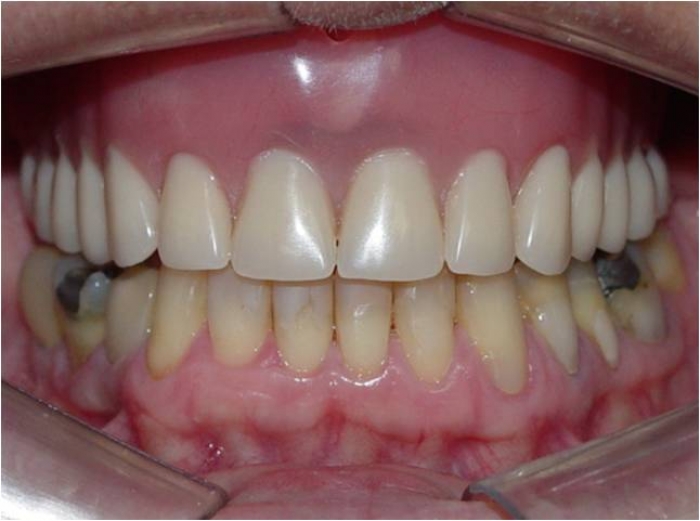

Imagem inicial

Sorriso final, do caso terminado em fevereiro de 2014